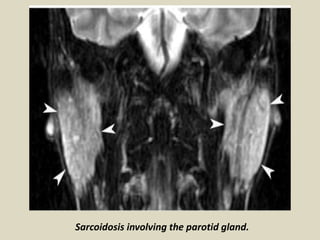

Sarcoidosis most commonly affects the salivary glands are rarely involved and usually manifests in

salivary glands. Parotid gland involvement occurs in 0.5-15 % of patients of sarcoidosis and may

Sarcoidosis involving the parotid gland.